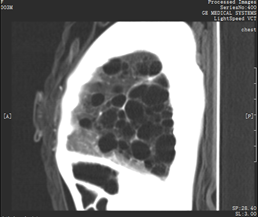

第2例患儿(3.23):一名3月大婴儿“童童”(化名),体重仅3.5kg,因为出生即诊断出严重的肺部先天性疾病,巨大“肺囊肿”,现已严重影响患儿呼吸和生长发育。从家长传来的影像学资料可以看出,童童心脏已被病变的肺挤压至右侧胸腔,严重程度可见一斑。如此小的体重年龄,合并如此大范围的肺部囊性病变伴肺气肿,童童所在的当地医院无奈的将她拒之门外。心急如焚的父母,一纸机票带童童从广东飞至上海,到心胸外科门诊时表现为气促、气喘、大汉淋漓,通过了流行病学调查及核酸检测,童童当晚被立即安排入院。诊断明确后立即安排急诊手术,心胸外科团队凭借丰富的胸部微创手术经验,在胸腔镜下行:“左肺下叶及左肺上叶部分切除术”,避免了童童小小年纪遭受“开胸”手术的痛苦,微创的伤口愈合完全,肺部情况恢复良好,现已顺利出院。